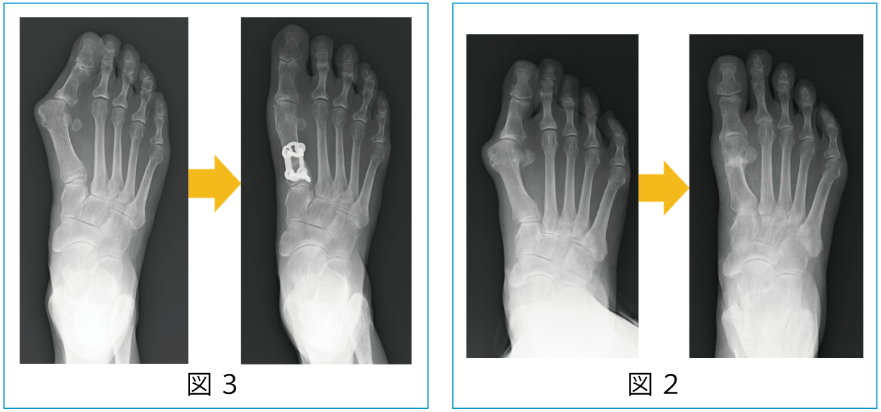

この手術では、骨の変形の部位や程度、矯正する角度に応じて骨切りする部位などが変わってきます。一番多いのは内側開大式高位脛骨骨切り術といって脛骨の内側を骨切りし開いて人工骨を挿入する方法(図1)です。他にも外側閉鎖式高位脛骨骨切り術や遠位大腿骨骨切り術(図2)、また場合によってはそれらを組み合わせた大腿骨・脛骨両側骨切り術(図3)などもあります。

外反母趾に対する骨切り術は非常に多くの術式がありますが、変形の程度などに応じて骨以外の軟部組織で矯正する方法と骨切りで矯正する方法があり、実際にはそれらを組み合わせて行います。骨切りについては変形が中等度までは第1中足骨遠位骨切り(ミッチェル変法)(図2)、変形が重度の場合は第1中足骨近位骨切り(マン変法)(図3)などが行われます。また足の裏に胼胝(たこ)ができたりする場合にはそれらに対して中足骨骨切り術などを併用します。術後はしばらくサンダル型装具を装着したりサポーターの装着が必要になります。